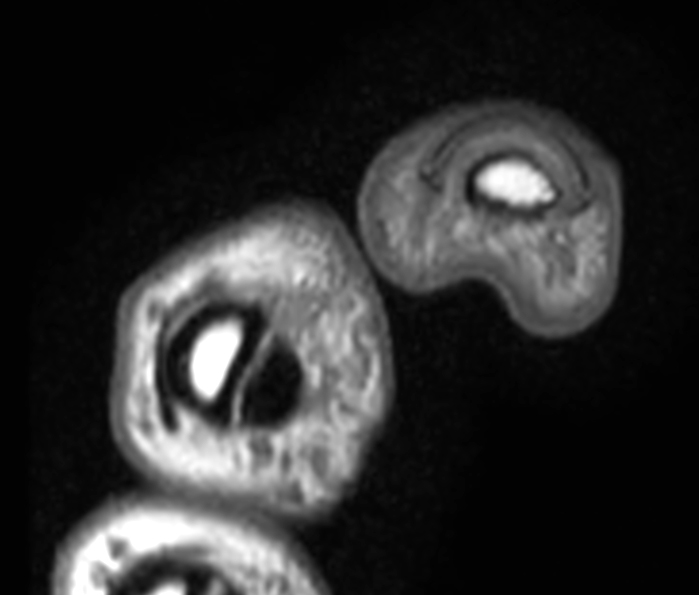

Patient with pathology on the thumb. ExamCard includes mDIXON XD TSE to achieve uniform, complete and consistent fat-free imaging. It simplifies the scan procedure by providing multiple image types in one single scan, including with/without fat suppression contrasts.

Axial T1w TSE